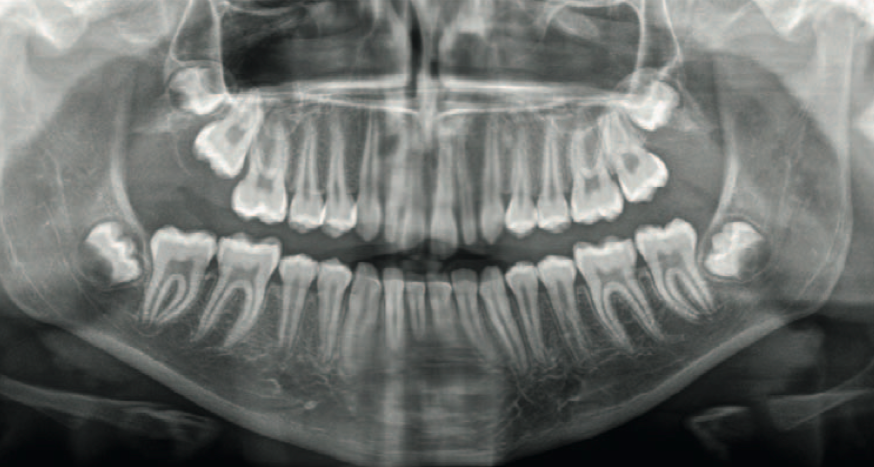

Streszczenie: Mikrodoncja jest schorzeniem, w którym wymiary jednego zęba lub więcej zębów są zmniejszone. Najczęściej dotyczy zębów 12 i 22. Mikrodoncja może występować w uzębieniu mlecznym i stałym. Pacjenci zgłaszają się do lekarza dentysty w celu poprawy estetyki uśmiechu. Leczenie wymaga postępowania interdyscyplinarego: ortodontycznego, zachowawczego, protetycznego oraz chirurgicznego. W artykule przedstawiono przypadki pacjentów z mikrodoncją oraz opisano możliwości terapii tej wady.

Mikrodoncja to schorzenie, w którym jeden ząb lub więcej zębów jest mniejszych niż normalnie [1]. Shafer, Hine, Levy klasyfikują ją na następujące typy:

Mikrodoncja pojedynczego zęba jest nierzadkim schorzeniem. Jedną z najczęstszych form zlokalizowanej mikrodoncji jest zaburzenie wymiarów i kształtu zęba 12 lub 22, który wówczas [...]